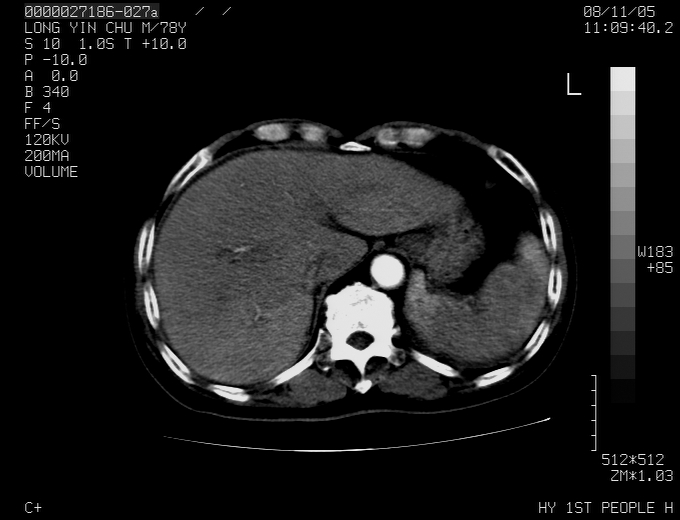

标题: CT16532:M78Y,肝脏病变,请会诊

腹胀,腹痛就诊,男性,78岁,外院b超未见异常。

考虑弥漫性肝癌并脾及双肾转移.双侧胸水.

考虑弥漫性肝癌并脾及双肾转移.双侧胸水.  支持

考虑弥漫性肝癌并脾及双肾转移,双侧胸水。